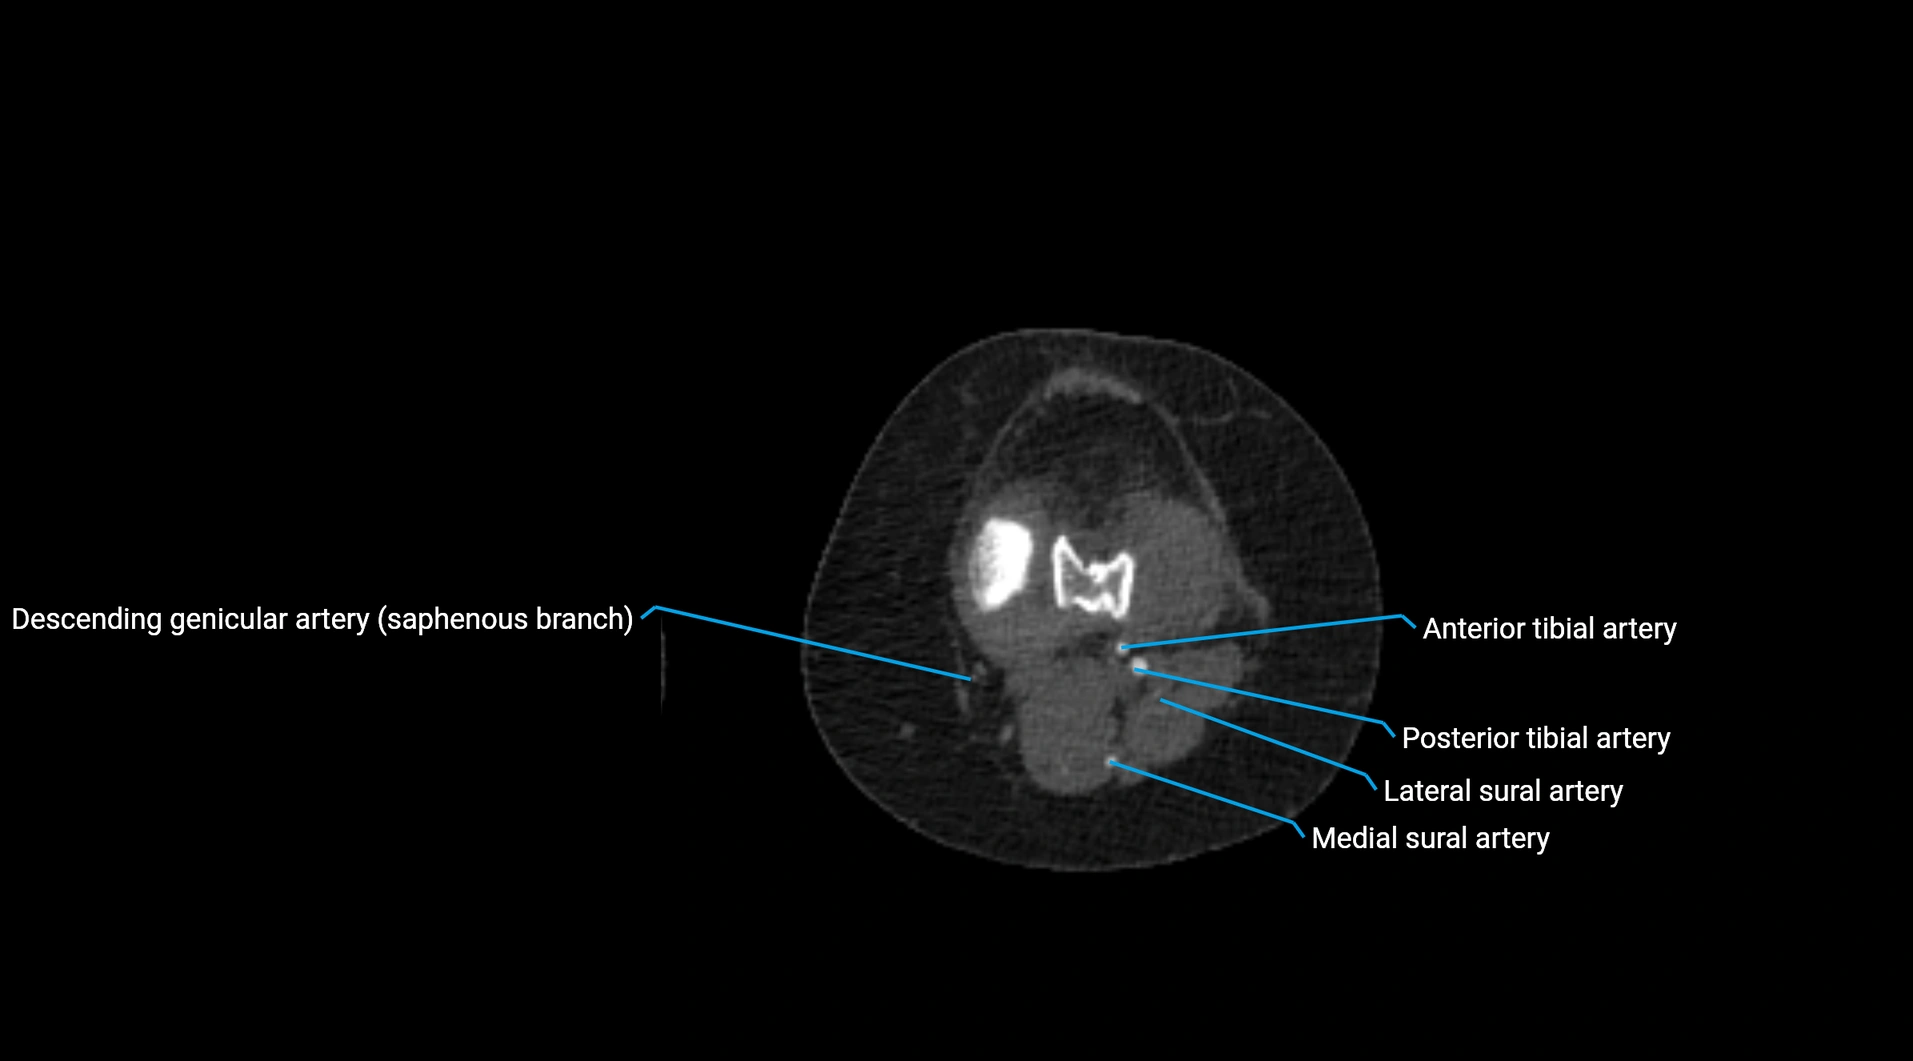

CT images

image